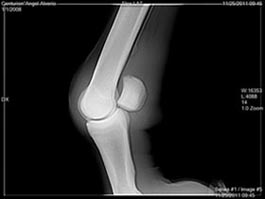

Another X Ray

Angel, I do not see a medial condylar fracture in these views. I would expect such a fracture to be best seen in a ap (front to back) view rather than a lateral view like we have above. There is a rather significant piece of bone fragment, often called a joint mouse, seen in the first image above however. DrO